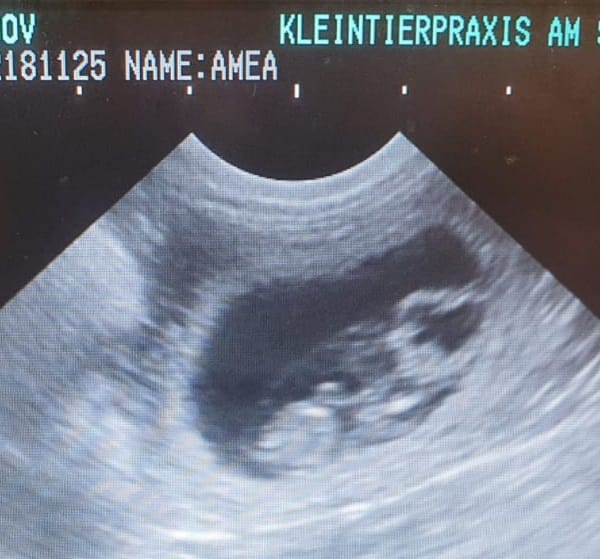

Unser kleines "E" zeigt sich von seiner Besten Seite

18.02.2022 29.Tag Wir haben Ultraschall gemacht und sind sehr glücklich. Durch Ultraschalluntersuchung kann die Trächtigkeit nachgewiesen werden. Zu diesem Zeitpunkt sind die Fruchtanlagen so groß, dass sie i.d.R. gut sichtbar sind, aber noch zu klein, um die Anzahl der Fruchtanlagen zu bestimmen. Wir haben die Gewissheit das es kein Einzelkind ist.